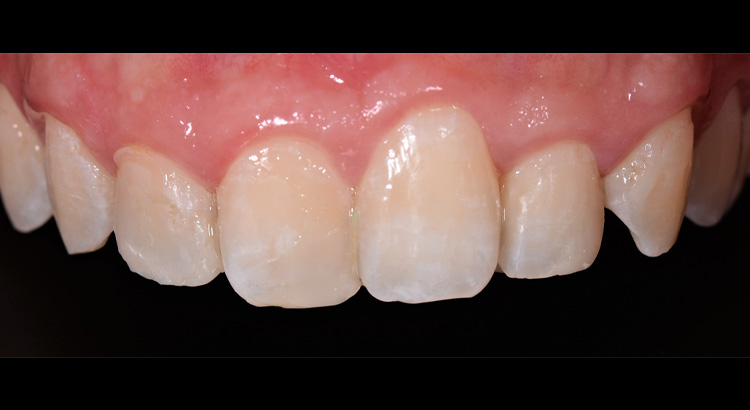

Odontoiatria Estetica

Questo giovane paziente vuole migliorare l’estetica del suo sorriso preservando però il suo dente da eventuali interventi sullo smalto. In particolare vuole cambiare la forma dell’incisivo centrale e diminuire gli spazietti neri tra gli incisivi laterali e i canini. Grazie all’utilizzo di materiali compositi ad alta esteticità è stato possibile ripristinare la corretta estetica del sorriso. Paziente contentissimo del suo nuovo sorriso.